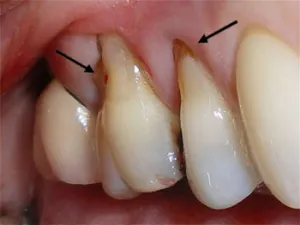

When recession of the gingiva occurs, the body loses a natural defense against both bacterial penetration and trauma. When gum recession is a problem, gum reconstruction using grafting techniques is an option.

When there is only minor recession, some healthy gingiva often remains and protects the tooth, so that no treatment other than modifying home care practices is necessary. However, when recession reaches the mucosa, the first line of defense against bacterial penetration is lost.

In addition, gum recession often results in root sensitivity to hot and cold foods as well as an unsightly appearance of the gum and tooth. When significant, gum recession can predispose to worsening recession and expose the root surface, which is softer than enamel, leading to root caries and root gouging.